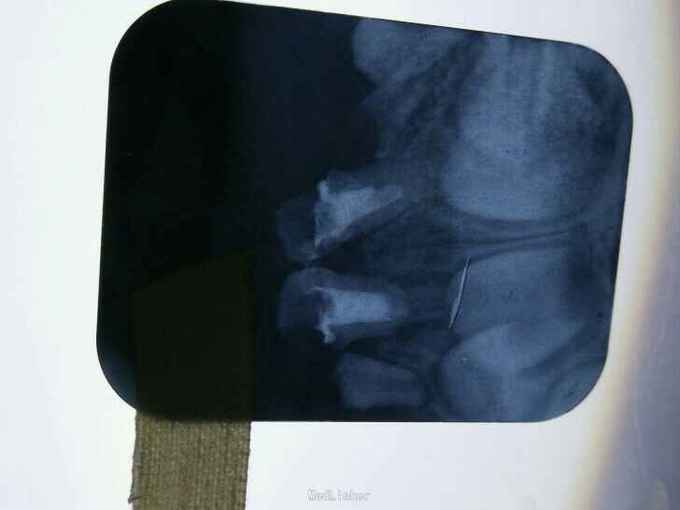

检查:51,61颈部环形龋,龋坏和龈缘齐平,色黑,质软,颊侧龋坏已达髓腔,无明显松动,冷热(-),叩(-),其他无异常 X线片示:牙根未吸收,根尖无暗影,其余无异常

诊断:51,61奶瓶龋 治疗计划:51.61rct+乳前牙透明冠修复 治疗: 1.51.61去软龋,行rct(见图1) 2.metapex根充,丁氧膏暂封(见图2.5) 3.乳前牙透明冠修复(见图3.4.)